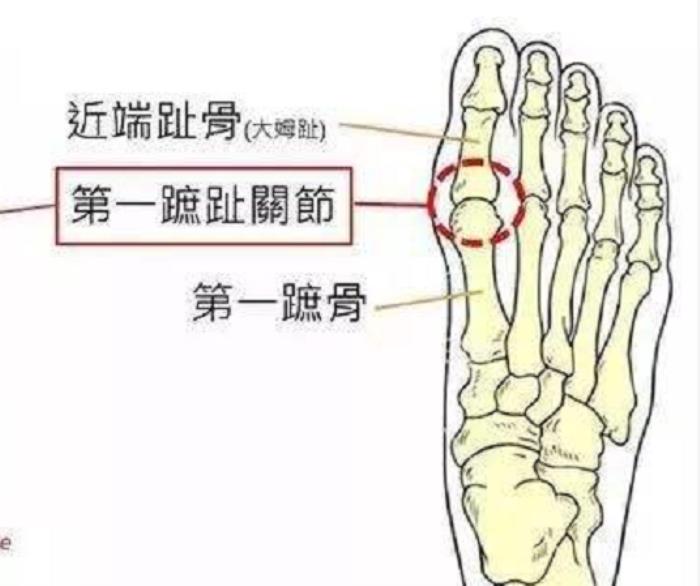

在走路的过程中,大拇趾需要做一个很重要的运动 —— 第一跖趾关节背屈 ——推蹬。

拇外翻不仅仅只是大拇趾向外侧移,同时与大拇趾相连的第一跖骨是向内侧移,另外足部的前足弓塌陷,涉及的关节不只是第一跖趾关节。